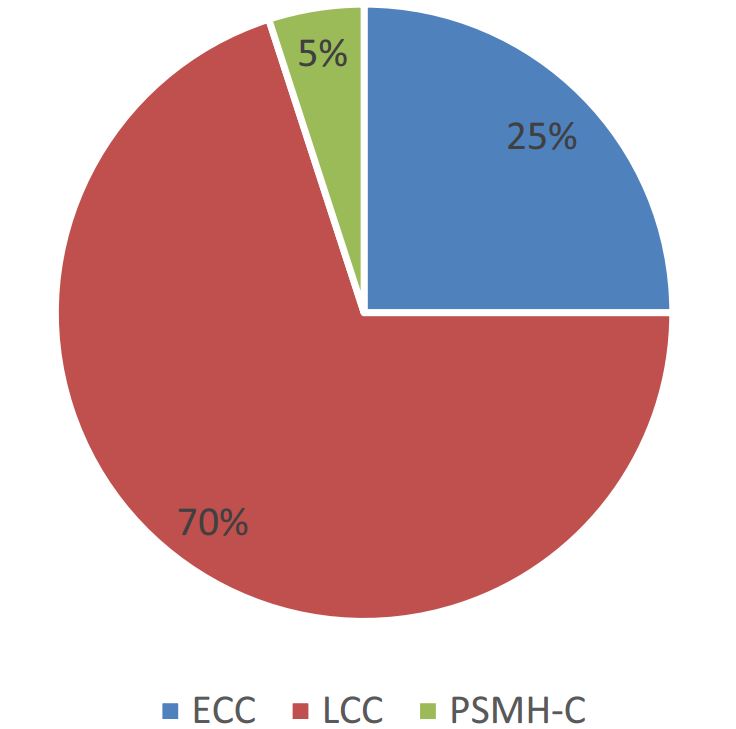

Trong một sơ đồ đánh giá 25 năm chăm sóc nha khoa trẻ em ở một đô thị, cung cấp dịch vụ chăm sóc nha khoa cho hơn 6000 trẻ em, từ trẻ sơ sinh cho đến trẻ 21 tuổi, thì quan sát được ba loại hình sâu răng chính (Martha Ann Keels, Erica A. Brecher, 2019) (Hình 1).

25% trẻ sâu bốn răng cửa sữa hàm trên, có thể có hoặc không có sâu các R4 sữa (Hình 2).

Loại hình sâu răng thứ hai ảnh hưởng đến phần lớn trẻ em là sâu kẽ, liên quan đến mặt xa R4 sữa và mặt gần R5 sữa (Hình 3).

70% sâu răng ở trẻ là thuộc nhóm LCC. Trẻ bị sâu LCC nghiêm trọng thường đặc trưng bởi tình trạng răng chen chúc, thiếu khoảng các răng sau. Sự đóng khoảng sinh lí giữa R4 và R5 sữa xảy ra vào tầm 4 tuổi.

Loại hình sâu răng thứ ba, ít phổ biến hơn cả, là sâu răng có liên quan đến thiểu sản men ở bốn R5 sữa (Hình 4).